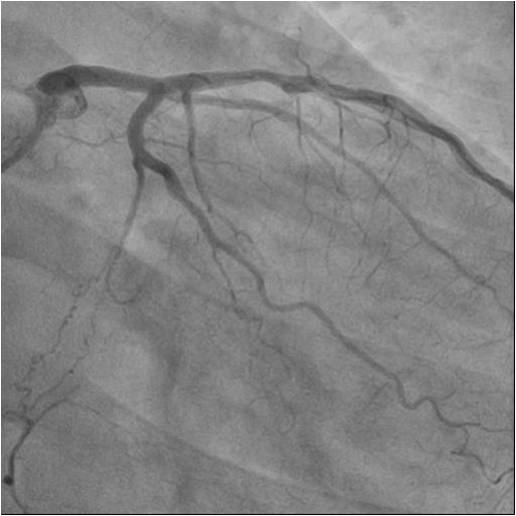

Relevant Catheterization Findings

Numerousattempts of antegraderecanalization using guidewires of different stiffnesswere unsuccessful. Pts ofretrograde recanalization using guidewires of different stiffnesswereunsuccessful. Another attempt at antegraderecanalization led to dissection dista RCA. Retrograde recanalization was performed using the technique of «kissing-wire». retrograde guidewire was inserted into theproximal segment of the RCA. Guidewire was externalized into the guide catheterusing Reverse CART technique. The tip-in technique was used for the Corsairantegrade microcatheter over the retrograde wire. Tthe microcatheterwassuccessfully inserted into the distal segment of the RCA. A soft antegradeguidewire was placed. A balloon catheter 2.0x30 mm was used for predilation inthe proximal middle and distal segments of the RCA at 14 atm. Consecutive DES2.75x44mm, DES 2.75x44mm, DES 3.5x39 mm stents were implanted in the distal,middle and proximal segments of the RCA, at pressures up to 16 atm.